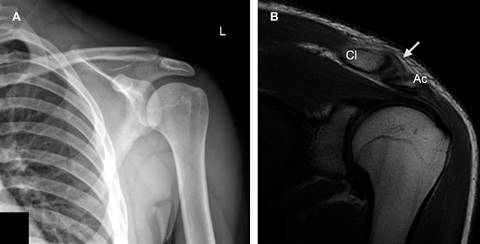

En la RM se observa edema óseo del extremo distal de la clavícula, edema de los tejidos blandos periarticulares (Figura 1) y ruptura del ligamento acromioclavicular superior con discreto incremento del espacio de 7.5 mm (Figura 2).

Figura 2: A) Radiografía anteroposterior de hombro izquierdo. Sutil elevación del extremo distal de la clavícula (Cl) e incremento del espacio coracoclavicular de hasta 14 mm. B) RM coronal T2. Leve ensanchamiento de la articulación acromioclavicular y ruptura del ligamento acromioclavicular superior (flecha blanca).